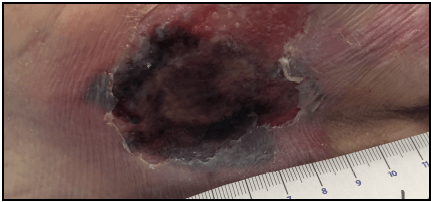

How wound you describe this wound?

- pink, red, black

- moist/ bleeding in areas

- dry, flakey skin surrounding wound

- what does this feel like? is there an odor? how much drainage?

What would you do for this wound?

-clean it

-measure it

-dress it (*there are many options!)

-alert MD

-wound consult

-safety report if thought to be pressure related